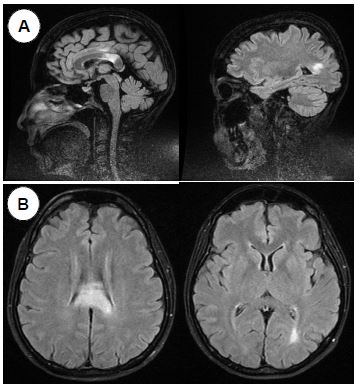

La tomografía abdominal sin contraste mostró una tumoración sólida de probable origen neoformativo en espacio pararrenal anterior izquierdo (retroperitoneo) parcialmente valorada por falta de la fase contrastada, asociada a adenopatías retroperitoneales ipsilaterales (figura 1). La resonancia magnética nuclear (RMN) mostró alteración de la señal en la medula espinal de la región cervical y dorsal de C5 a T10, luego de la administración de contraste se observa áreas de realce en esas regiones. Los cuerpos vertebrales sin evidencia de lesiones expansivas ni colapsos (figura 2). Además, la RMN encefálica evidenció lesiones desmielinizantes en la región posterior del tronco del cuerpo calloso, en la región posterior de los cíngulos a predominio izquierdo y en la región posterior al cuerno occipital del ventrículo lateral izquierdo (figura 3).

Enfermedades inflamatorias desmielinizantes del SNC: En un paciente con MT es mandatorio realizar una RMN de encéfalo con gadolinio para diagnosticar lesiones desmielinizantes asintomáticas asociadas. Las lesiones multifocales en médula espinal y encéfalo hacen sospechar una enfermedad desmielinizante del SNC en nuestra paciente. Estas son: la esclerosis múltiple (EM) la encefalomielitis diseminada aguda (ADEM), el espectro de enfermedad de la neuromielitis óptica (NMOSD) y la enfermedad por anticuerpos anti-MOG. En la EM la lesión medular es de menor extensión que la presentada por la paciente. Las lesiones en encéfalo tampoco son típicas de EM (7). De estas las que presentan una lesión extensa en la medula espinal (MTLE) son característicamente la NMOSD y enfermedad por anti MOG (glicoproteína de la mielina del oligodendrocito). Esta paciente tiene un cuadro clínico e imágenes compatibles con NMOSD.

La NMOSD se caracteriza por presentar ataques agudos y recurrentes de MT o neuritis óptica (8). También pueden presentar síntomas encefálicos como nauseas intratables, hipo, encefalopatía o somnolencia. La lesión medular es frecuentemente una MTLE como en nuestra paciente. Las lesiones encefálicas pueden localizarse en el área postrema del bulbo (causando náuseas, vómitos e hipo) (9, 10), tronco cerebral, diencéfalo (causando sueño excesivo diurno, SIADH) (11) y lesiones peri ependimarias extensas en cuerpo calloso. La hiperintensidad extensa en el cuerpo calloso y la MTLE es muy sugerente de NMSOD en esta paciente. La etiología de esta enfermedad es autoinmune; los anticuerpos identificados son los dirigidos contra la acuaporina 4 (anticuerpos anti-AQP4) (12). ANA y anti SSA/SSB son frecuentes en la NMOSD, los cuales también presenta esta paciente. La enfermedad por anticuerpos anti-MOG comparte algunas similitudes con NMOSD, aunque se asocia más frecuentemente con síntomas parecidos al ADEM y las lesiones medulares suelen ser múltiples (13), las cuales no presenta nuestra paciente.

Nuestra paciente, mujer de 49 años, presenta un cuadro subagudo de dolor abdominal y paraparesia inicialmente asimétrica. La paraparesia progresa, encontrándose hallazgos clínicos de primera neurona motora (paraparesia espástica), compromiso autonómico (globo vesical y estreñimiento) y nivel sensitivo en D5, diagnosticándose clínicamente un síndrome medular. La RMN medular muestra una lesión intramedular cérvico dorsal (C5-T10), con captación de contraste, compatible con una MTLE. La RMN cerebral confirma la presencia de múltiples lesiones periventriculares (cuerpo calloso, ventrículo izquierdo) sin captación de contraste. Ambas lesiones (medulares y cerebrales), compatibles con enfermedad desmielinizante. El estudio de LCR fue normal. Se encontró una masa abdominal (adenopatía) compatible con un Linfoma de Hodgkin clásico en anatomía patológica.

En nuestra paciente se encontraron lesiones tipo MTLE y lesiones en sustancia blanca periventriculares en los estudios de RMN con contraste. Las lesiones medulares fueron de preferencia centrales con captación de contraste. Las lesiones encefálicas no captaron contraste. Los reportes en la literatura no son diferentes a nuestros hallazgos.